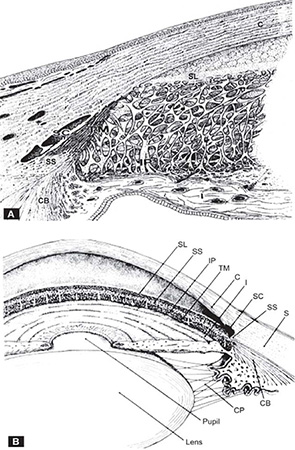

FIGURES 1.1A and B: Diagrams showing the development of the iris and ciliary body. The two layers of neuroectoderm forming the edge of the optic cup cover the ciliary muscle and then extend onto the posterior surface of the papillary membrane.From Snell RS, Lemp MA. Clinical Anatomy of the Eye, 2nd edition, Blackwell Science, 1998)

The sulcus extends anteriorly from Schwalbe's ring, which is the termination of Descemet's membrane, to the scleral spur posteriorly (Figures 1.2A and B). It accommodates the canal of Schlemm externally, and the corneoscleral portion of the trabecular meshwork internally.

FIGURES 1.2A and B: Semi-diagrammatic representation of the structures of the angle of the anterior chamber. (A) Enlarged view of the trabecular meshwork. Superimposed trabecular sheets with intra-and intertrabecular spaces through which aqueous humor flows to reach Schlemm's canal. (B) Composite gonioscopic and cross-sectional view of the anterior segment of the eye. SL = Schwalbe's line, SS = scleral spur, IP =iris process, TM = trabecular meshwork, C = cornea, I = iris, SC = Schlemm's canal, S = sclera, CB = ciliary body, Z = zonules.(From Tripathi RC and Tripathi BJ in Duane TA and Jaeger EW (eds) (1982) Biomedical Foundations of Ophthalmology, Vol. 1, published by Harper and Row)

The trabecular meshwork is a sieve-like structure of connective tissue beams arranged as superimposed perforated sheets. It bridges the scleral sulcus, extending from Schwalbe's ring anteriorly, to the scleral spur and junction of iris and ciliary body posteriorly. The meshwork is divided into three layers. The uveal meshwork is innermost; closer to Schlemm's canal, and connected to the spur is the corneoscleral meshwork. Closest to the endothelial lining of Schlemm's canal is the cell-rich zone of the juxtacanalicular or cribiform meshwork (Figure 1.3). The spaces in the meshwork sheets progressively decrease in size moving outward. Hydrophilic glycosaminoglycans and collagenous material in the extracellular spaces must influence the outflow resistance.